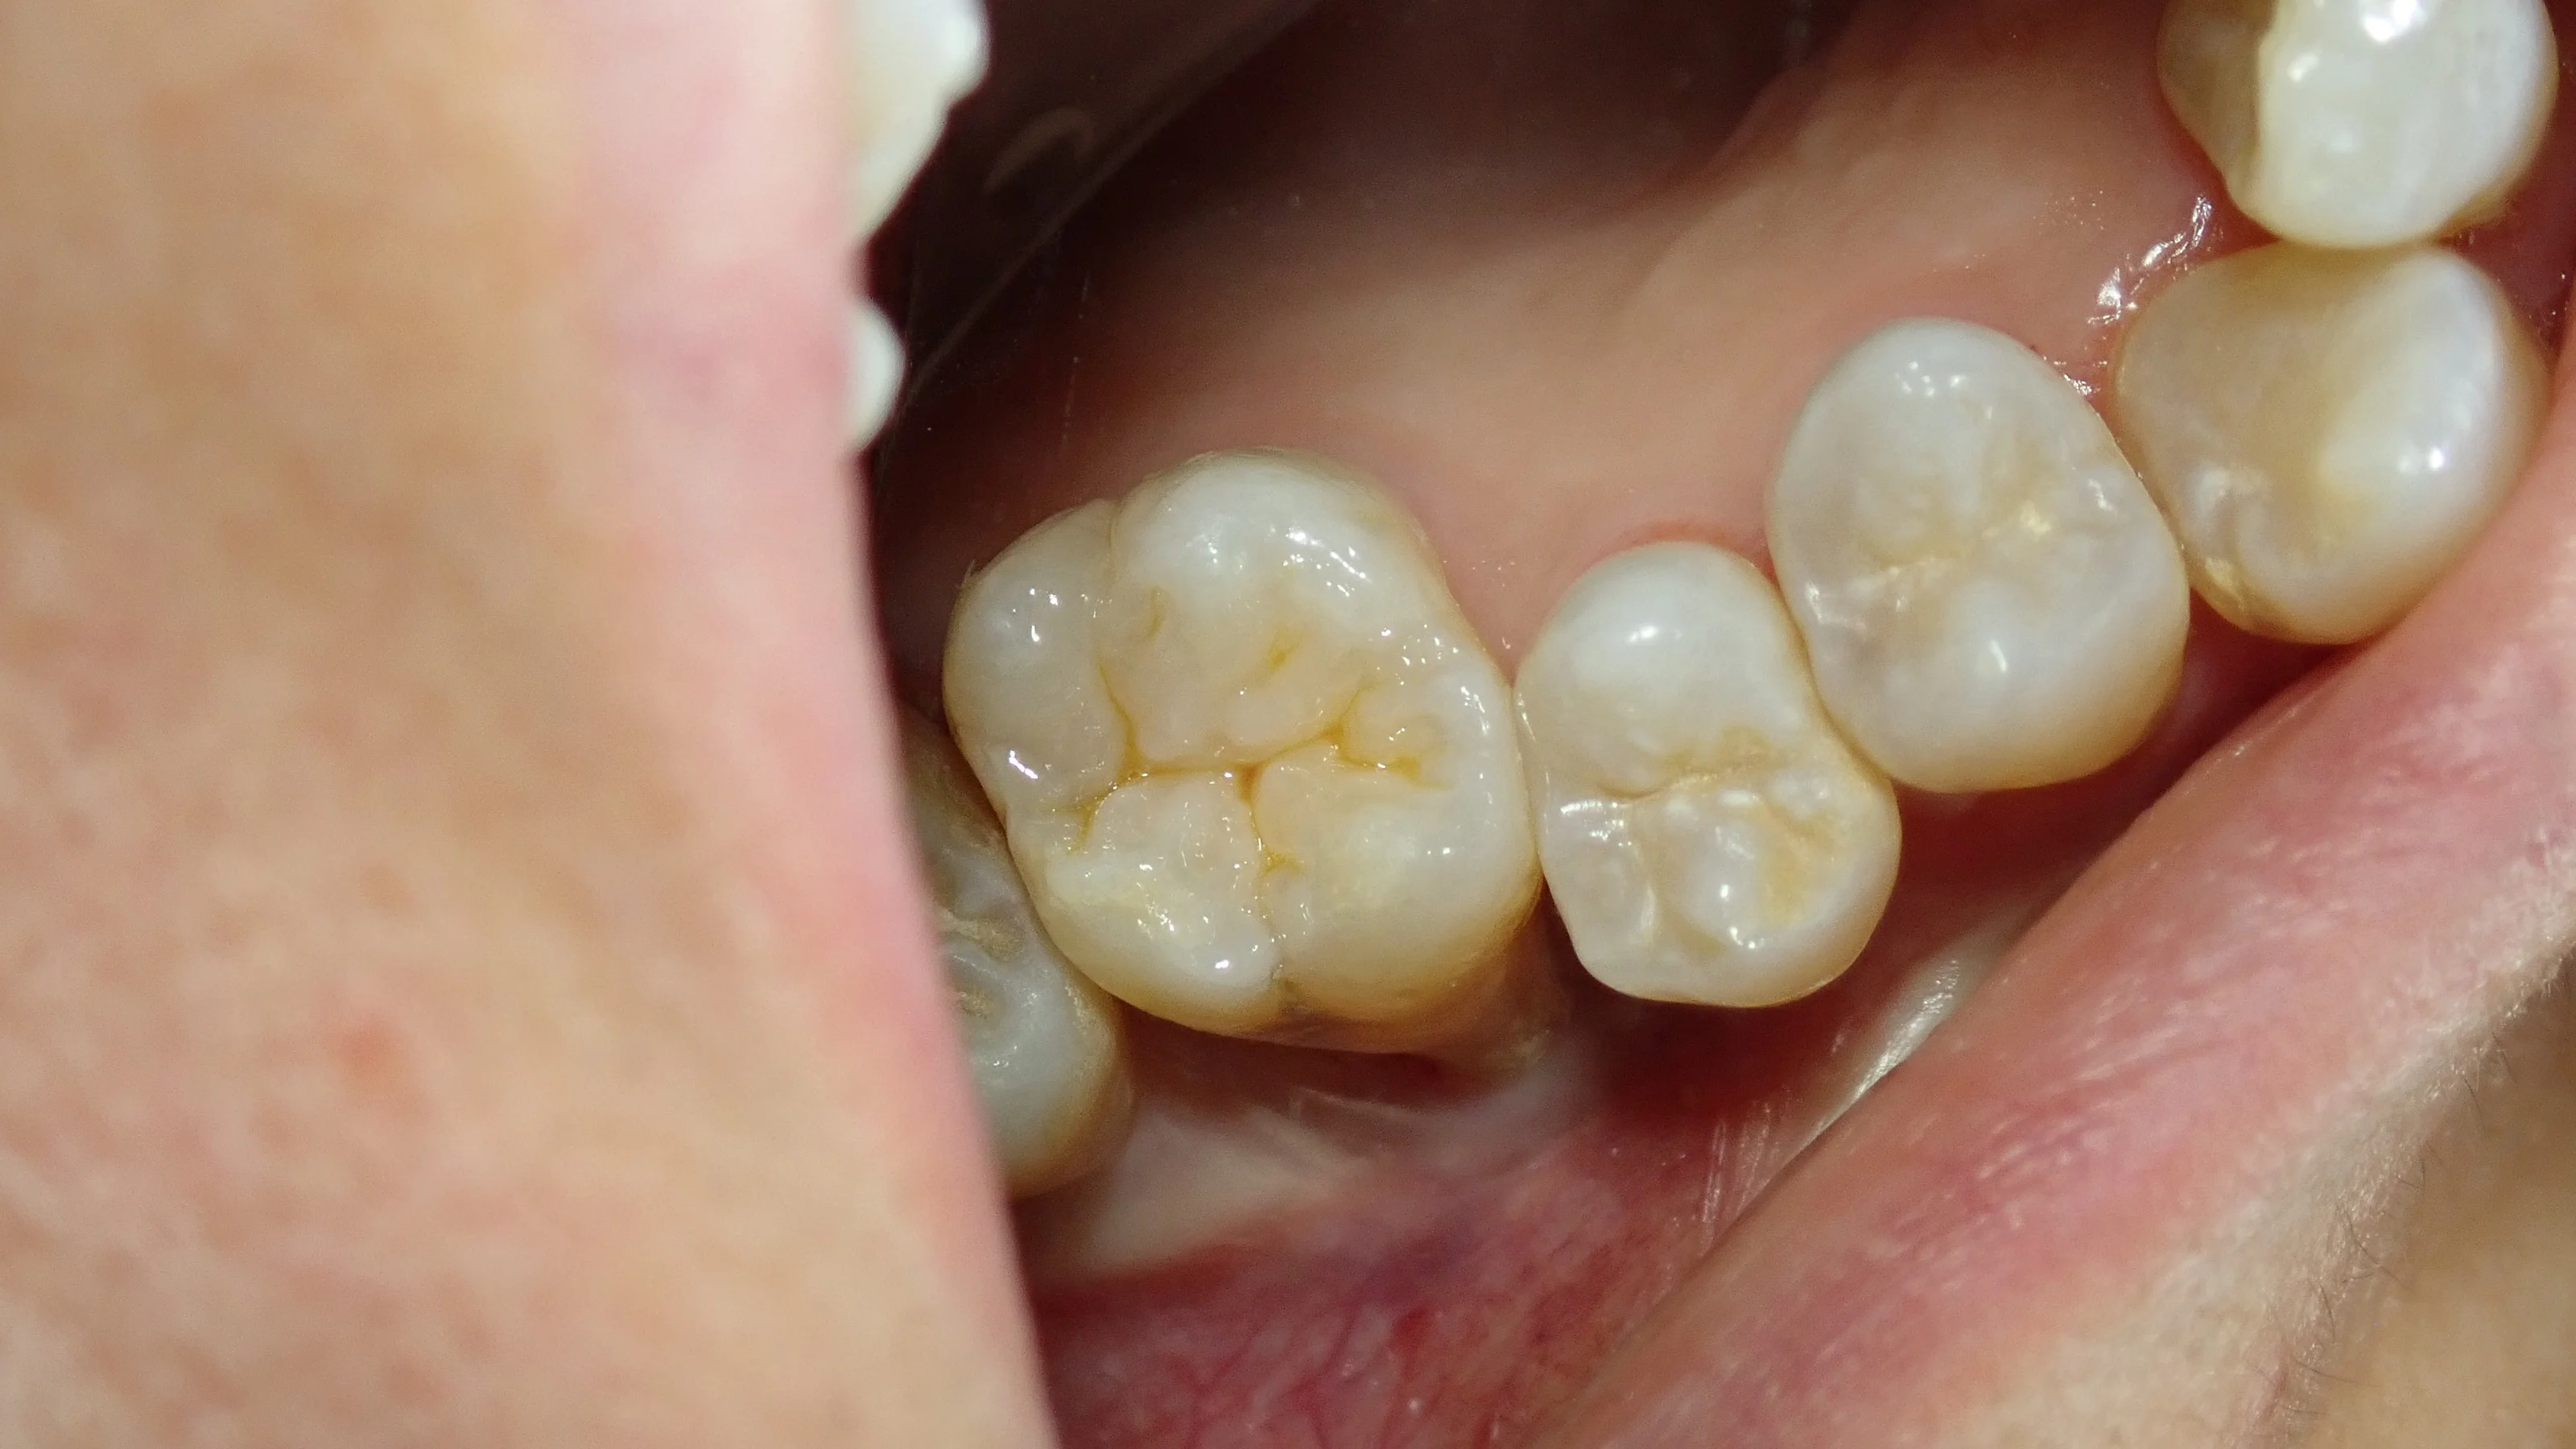

で、詰め終わったのがこちら。

手前の歯とかは着色もそんなに強くないタイプだったので、ステインは薄めにしました。

それでも、裂溝部を再現するとしないとでは天然の歯っぽさが全然ちがいますので、やはりあった方が自然だと思います。